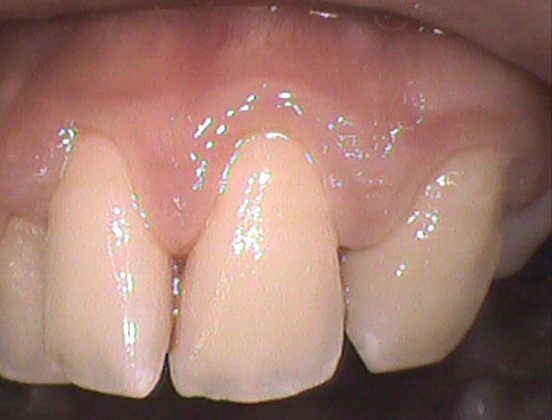

◎クリーニング後

綺麗になりました✨

歯間のお掃除をする習慣がない方は歯周炎のリスクが高くなってしまいます😰

歯周炎とは歯肉炎(一時的な歯肉のみに起こる炎症)が進行して、歯槽骨(歯を支える骨)が溶けてなくなってしまう病気です。

なるべく一日一回はフロスを使えるといいですね◎